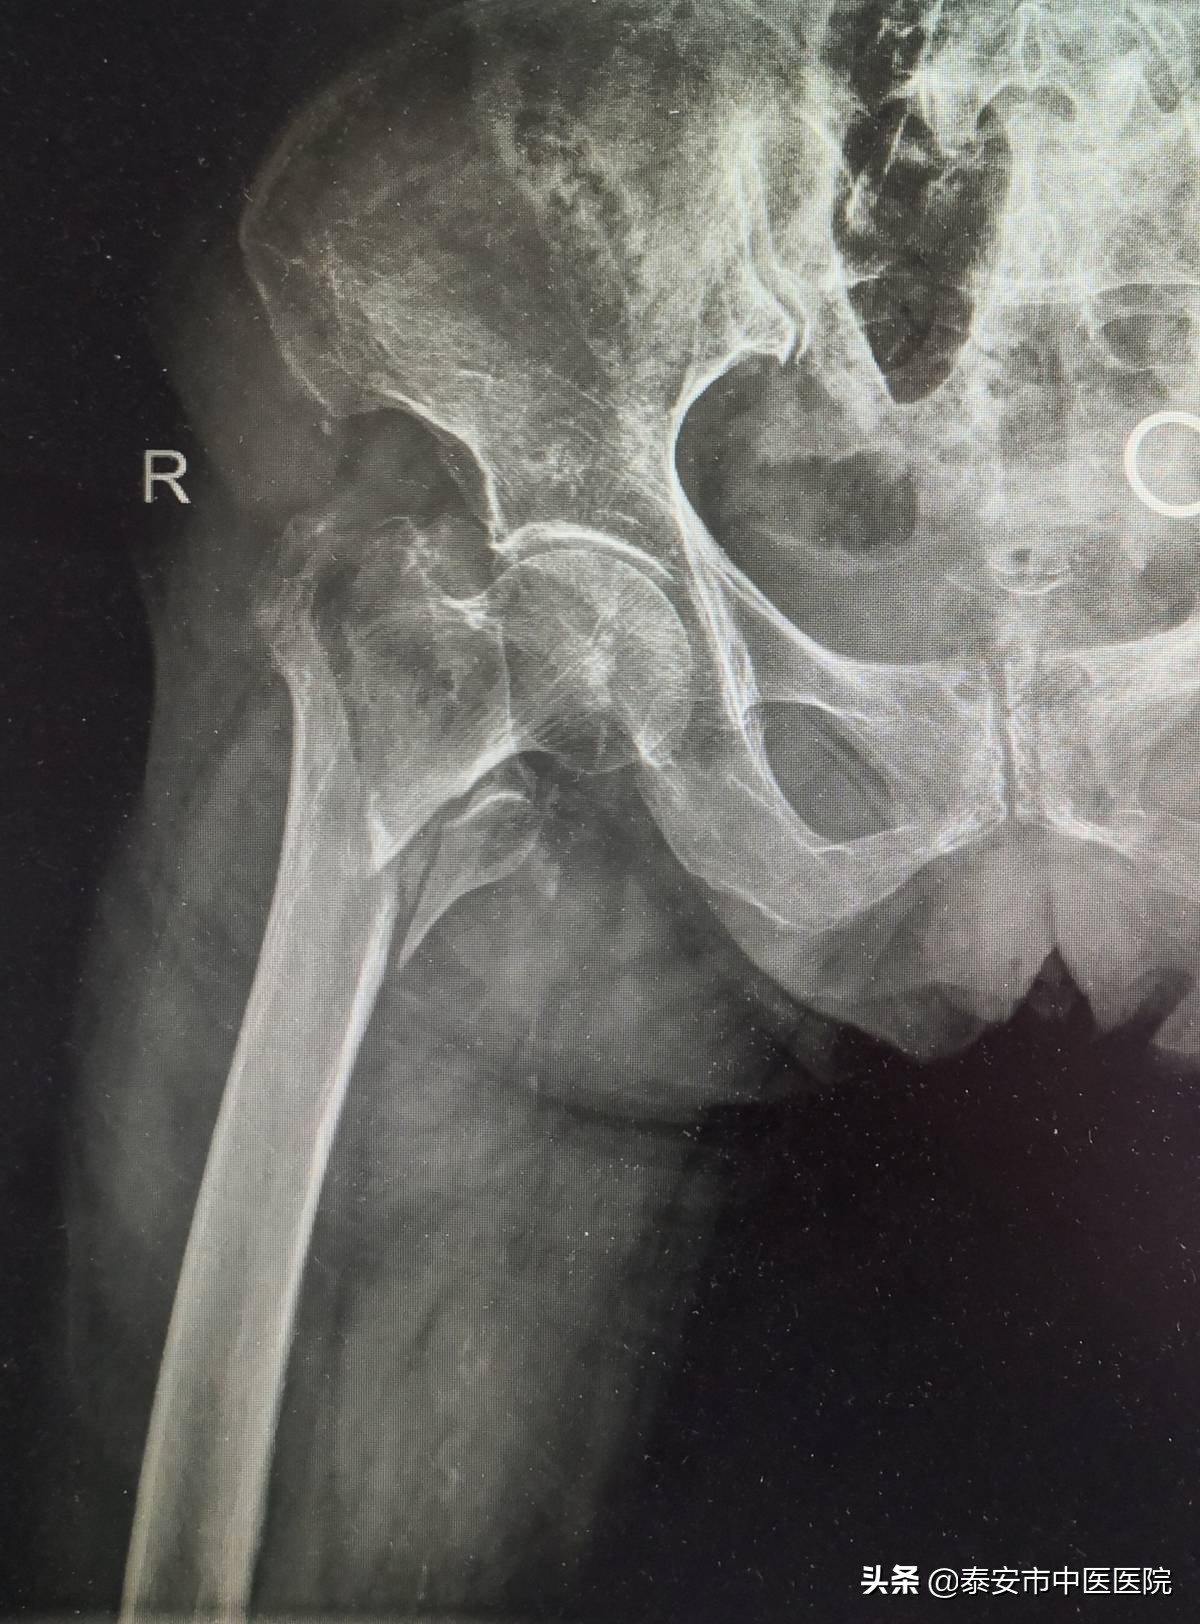

随着社会人口老龄化的发展,中老年人骨折发生率逐年上升,若治疗不当,会出现严重并发症,大大缩短患者的预期寿命,针对此类骨折,保守治疗由于卧床时间太长,易发生深静脉血栓,褥疮,肺部感染等并发症,危及患者生命。该室采用微创经皮内固定治疗股骨粗隆间骨折,具有手术创伤小(切口仅4cm左右),住院时间短,痛苦少,恢复快等优势特点,能让患者迅速恢复正常活动,减轻了患者家庭负担。

微创经皮内固定治疗股骨粗隆间骨折